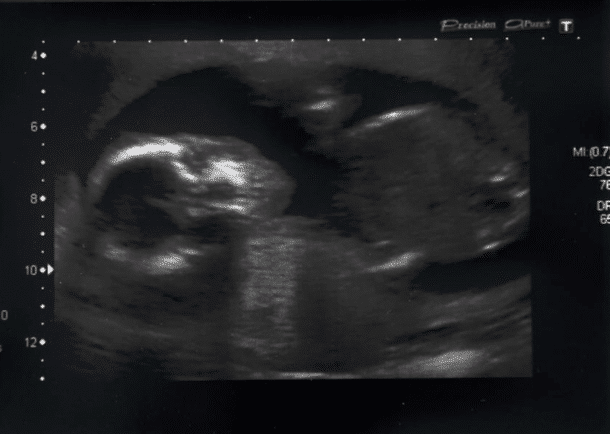

Alors qu’elle se remettait de cette épreuve, elle sentait quelque chose d’étrange se passer dans son corps. En effet, son ventre gonflait quand même de façon inquiétante. Elle a d’abord pensé que c’était une conséquence de la fausse couche mais elle a préféré consulter. Alors les médecins lui ont refait une échographie.

C’est à ce moment là qu’ils ont détecté qu’il y avait un second bébé ! Qui lui s’était bien développé dans l’utérus de Sadie et qui se portait bien. Sa présence n’avait pas pu être détectée pendant les échographies passées pendant la fausse couche en raison des importantes pertes de sang.